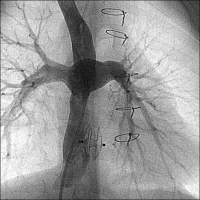

Die Fontan-Operation als definitive Palliation bei funktionell univentrikulären Herzen

Journal für Kardiologie - Austrian Journal of Cardiology 2012; 19 (11-12): 324-331 Volltext (PDF) Summary Fragen zum Artikel Abbildungen